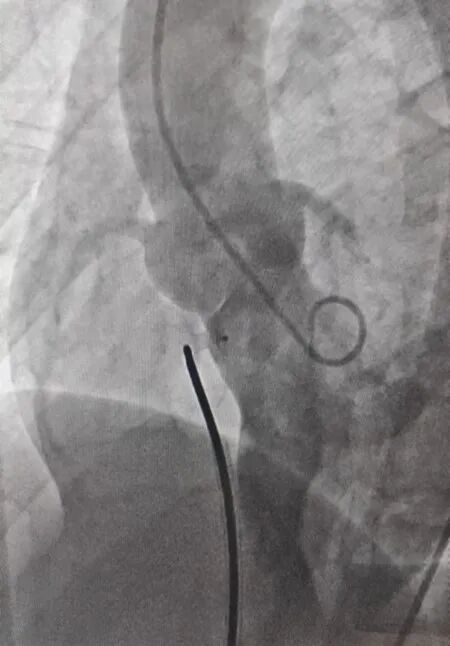

术前造影

随后经室间隔中间分流口建立经股动-静脉工作轨道,输送一枚ABFDQ-Ⅱ 08(封堵器腰高5mm x 腰部直径8mm) MemoSorb®全降解封堵器,在超声引导下,经过中间分流释放左盘面,牵拉确认释放稳定后释放右盘面,完成释放后超声提示封堵器骑跨缺损部位两侧,几乎无残余分流,故锁紧成型线使封堵器由葫芦状完全成“工”字型,最终超声显示封堵器位置良好,无残余分流,未对流出道、主动脉瓣、二尖瓣及三尖瓣产生较大影响,封堵效果理想,手术圆满成功!

传统封堵器术后造影 全降解封堵器术后造影